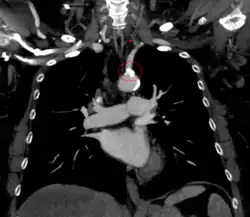

CT angiography of subclavian steal phenomenon